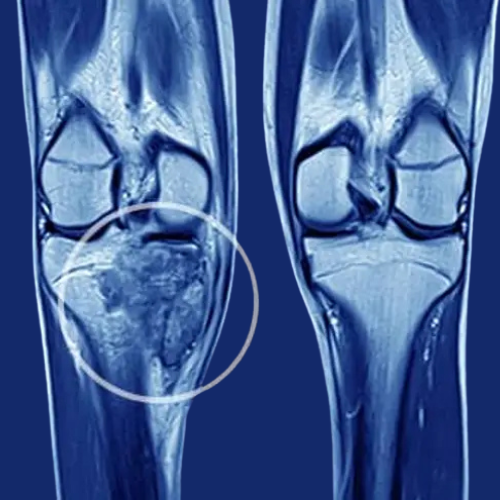

1. Knee Replacement (Partial & Total) by Dr. Rajesh Mishra

Knee Replacement, including partial and total procedures, is performed to treat severe knee arthritis, injury, or degeneration. In partial replacement, only the damaged portion of the joint is replaced, while total replacement involves replacing the entire joint with an artificial implant. The surgery helps relieve chronic pain, improve flexibility, and restore mobility. Patients benefit from better function, enhanced quality of life, and the ability to perform daily activities with greater ease.